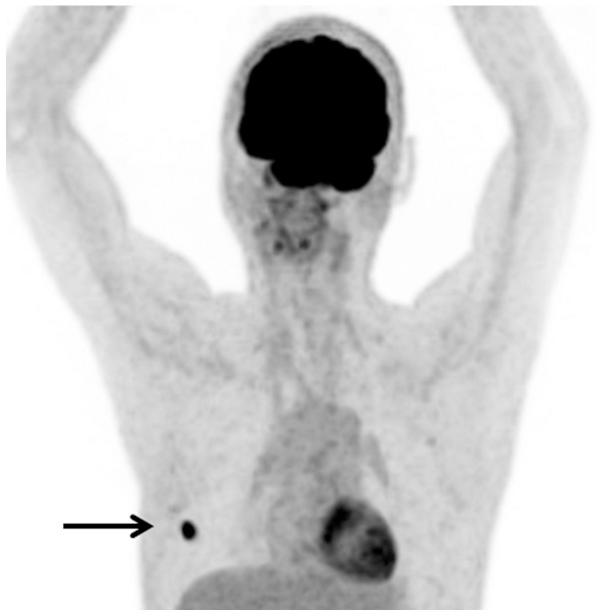

Gastrointestinal stromal tumors (GISTs) are the most frequently diagnosed mesenchymal tumors of the GI tract. GISTs usually arise from the stomach, followed by the small intestine, rectum and other locations in the GI tract. The most common metastatic sites are the liver and peritoneum, whereas GISTs rarely metastasize to the bone. Although a small number of previous studies have described bone metastases originating from GISTs, the true prevalence is yet to be elucidated. The present study describes two cases of bone metastasis in patients with GISTs and reviews the relevant literature. Case one was of a 78-year-old male who presented with bone metastasis to the femoral neck five years after the resection of a GIST. The metastasis was completely resected and the patient remains alive nine years after the initial diagnosis of the GIST. Case 2 was of a 41-year-old male who presented with bone metastases to the ribs following resection of GISTs seven and 17 years earlier. The metastases were completely resected and the patient remains alive 17 years after the initial diagnosis. In total, only 10 cases of GISTs with metastases to the bone have been reported in the English literature. The possibility of bone metastases originating from a GIST should be considered during clinical follow-up, particularly in the presence of liver metastases. If feasible, bone metastases should be completely surgically excised.

胃肠道间质瘤(GISTs)是胃肠道最常被诊断出的间叶组织肿瘤。GISTs通常起源于胃,其次是小肠、直肠和胃肠道的其他部位。最常见的转移部位是肝脏和腹膜,而GISTs很少转移至骨骼。尽管此前有少数研究描述过起源于GISTs的骨转移情况,但真实患病率仍有待阐明。本研究描述了2例GISTs患者发生骨转移的病例,并对相关文献进行了综述。病例1为一名78岁男性,在GIST切除术后5年出现股骨颈骨转移。转移灶被完全切除,患者在初次诊断GIST后9年仍存活。病例2为一名41岁男性,分别在7年前和17年前切除GIST后出现肋骨骨转移。转移灶被完全切除,患者在初次诊断后17年仍存活。英文文献中总共仅报道了10例GISTs发生骨转移的病例。在临床随访期间,尤其是存在肝转移的情况下,应考虑GISTs发生骨转移的可能性。如果可行,骨转移灶应通过手术完全切除。